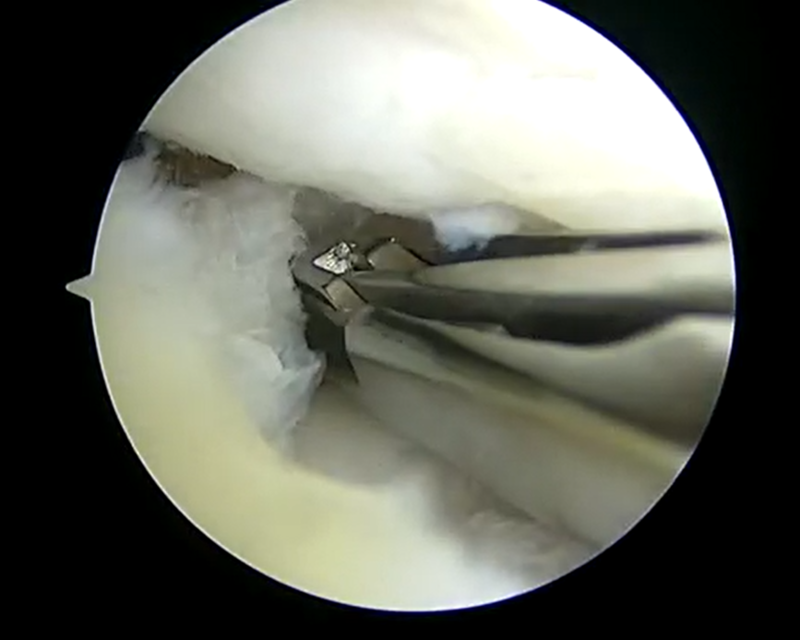

| 内側半月板問題なし | 外側半月板フラップ損傷 | 大腿骨側の軟骨損傷部 |

| 翻転していた外側半月板損傷部の整復 | 外側半月板損傷部の切除 | 外側半月板損傷部の切除後 |

今回は軟骨損傷により剥がれた軟骨片や半月板の断裂によるフラップ部分の引っ掛かりとそれにより膝の伸びが完全に出ないのが一番の問題と捉えて関節鏡視下手術を施行しました。術後膝が伸びないのが後方の筋腱拘縮の問題もありリハビリテーションも効果がとてもありました。